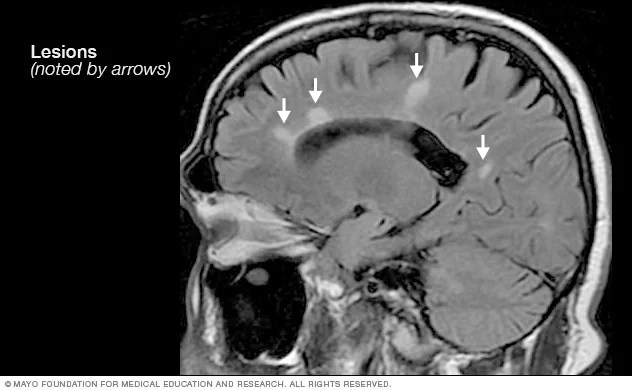

Lesion: An area of damage or scarring in the central nervous system caused by MS. Interchangeable with sclerosis or scarring.

Magnetic Resonance Imaging (MRI): A medical imaging technique used in radiology to create detailed images of organs and tissue. MRI uses a strong magnetic field and computer-generated radio waves. There is no radiation exposure to the patient. MRI can show demyelination of the central nervous system and is a powerful tool for diagnosing and monitoring MS.